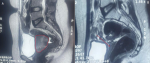

Chronologie: en janvier 2024, la patiente a présenté un épisode d'avortement spontané suivi de saignements persistants et de pertes blanchâtres, conduisant à une consultation gynécologique au cours de laquelle une masse bourgeonnante et saignante du col utérin a été mise en évidence. Une première biopsie réalisée le 9 janvier 2024 a suggéré un processus tumoral utérin, conduisant à une relecture anatomopathologique et à de nouvelles biopsies le 25 janvier 2024. Le 30 janvier 2024, l'examen histopathologique a évoqué un carcinome à cellules claires du col de l'utérus, nécessitant une confirmation immunohistochimique. Le 19 février 2024, la tomodensitométrie thoraco-abdomino-pelvienne n'a pas révélé de métastase. Le 22 février 2024, l'étude immunohistochimique a confirmé le diagnostic. Le 27 février 2024, l'imagerie par résonance magnétique (IRM) abdomino-pelvienne a montré une tumeur cervicale localement avancée de stade IIIA mesurant 36 x 50 mm avec des adénopathies iliaques externes gauches. Entre le 28 avril et le 4 juin 2024, la patiente a reçu une radiochimiothérapie concomitante. Le 16 juin 2024, l'IRM de contrôle a montré une disparition quasi complète de la tumeur. Le 18 juillet 2024, une colpohystérectomie élargie a été réalisée, et le 1er août 2024, l'examen anatomopathologique de la pièce opératoire n'a retrouvé aucun reliquat tumoral.

Démarche diagnostique: la démarche diagnostique a débuté par un examen gynécologique complet suivi de biopsies cervicales initiales. En raison d'une discordance entre les données cliniques et la première biopsie, une relecture anatomopathologique associée à de nouvelles biopsies a été demandée. L'examen histologique a montré une prolifération tumorale faite de massifs solides avec de rares structures glandulaires, constituée de cellules polygonales à cytoplasme clair ou éosinophile modérément abondant, avec des atypies cytonucléaires marquées et de nombreuses mitoses. Le stroma était fibro-œdémateux avec congestion vasculaire et suffusions hémorragiques, sans signe de différenciation malpighienne (Figure 1, Figure 2). L'étude immunohistochimique a montré une expression nucléaire focale de p16, sans expression de p63 ni de P40, confirmant un adénocarcinome à cellules claires du col de l'utérus. La tomodensitométrie thoraco-abdomino-pelvienne n'a pas mis en évidence de métastases, tandis que l'IRM abdomino-pelvienne a montré une tumeur cervicale localement avancée avec adénopathies iliaques externes gauches (Figure 3, Figure 4). Les diagnostics différentiels envisagés comprenaient un carcinome épidermoïde du col de l'utérus et d'autres types d'adénocarcinomes cervicaux. Les données histopathologiques et immunohistochimiques ont permis d'écarter ces hypothèses et de retenir le diagnostic final de carcinome à cellules claires du col de l'utérus.

Figure 3: A) IRM avant traitement montrant une tumeur du col de l'utérus localement avancée, stade IIIA, mesurant 36 mm x 50 mm (cercle rouge); B) IRM après radiochimiothérapie montrant une disparition quasi-totale de la tumeur (flèche rouge)

Figure 4: A) IRM avant traitement montrant une tumeur du col de l'utérus localement avancée, stade IIIA, mesurant 36 mm x 50 mm (cercle rouge); B) IRM après radiochimiothérapie montrant une disparition quasi-totale de la tumeur (flèche rouge)